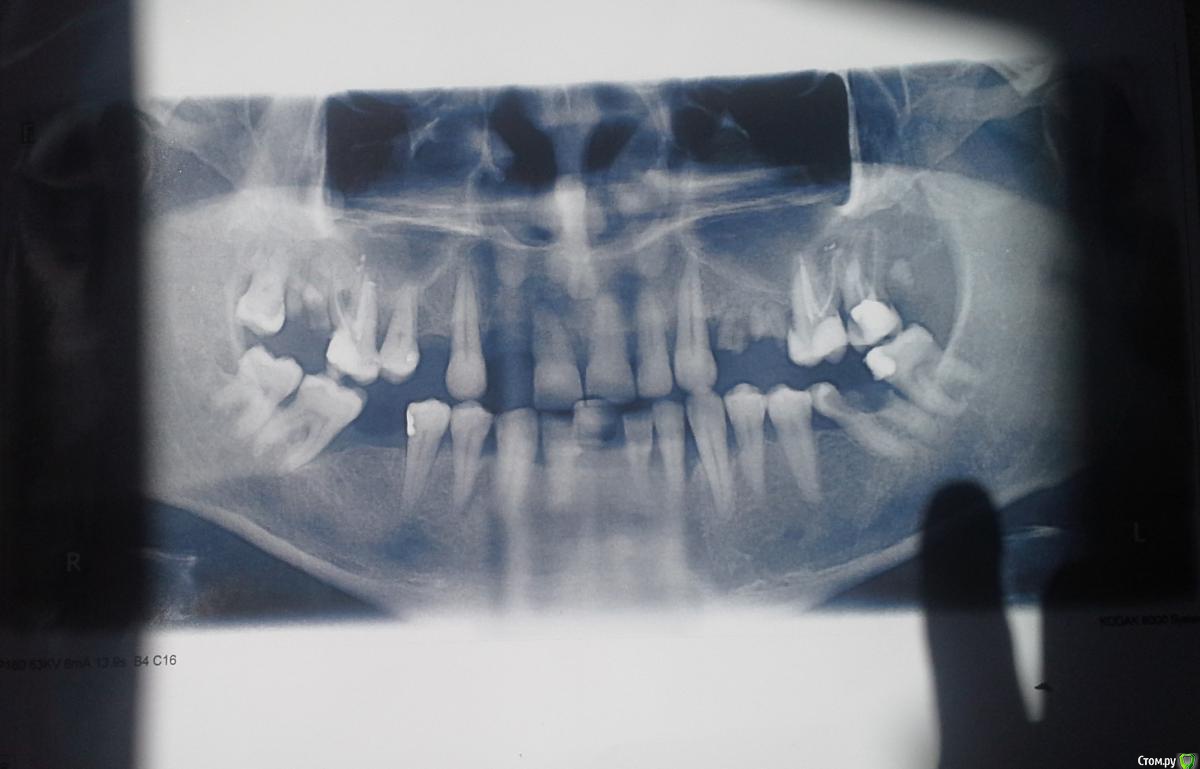

vicsem18 Опубликовано 9 июля, 2015 Поделиться Опубликовано 9 июля, 2015 (изменено) Добрый день! У меня отсутствуют зубы 15, 14, 21, 22, 24. Ходил на прием к врачу, выразил ему свое пожелание установить цельный мостовидный протез на зубы с 16-го по 25-й, ( 12, 11, 21, 22 – из металокерамики, остальные цельнолитые металические - чтобы не сильно обтачивать живые здоровые зубы), на что получил ответ, что такое невозможно, и нужно садить под металлокерамические коронки еще и 13 и 23 зуб. Так ли это на самом деле, и какую лучше применить конструкцию без обточки клыков, с металлокерамикой на 12-22 зубах ? Импланты не рассматриваю, с финансовым положением. Спасибо за внимание. Изменено 9 июля, 2015 пользователем vicsem18 Ссылка на комментарий

vicsem18 Опубликовано 9 июля, 2015 Автор Поделиться Опубликовано 9 июля, 2015 (изменено) Извиняюсь,не прочитал,есть снимок с еще не удаленным 21 зубом,сейчас его нет Изменено 9 июля, 2015 пользователем vicsem18 Ссылка на комментарий